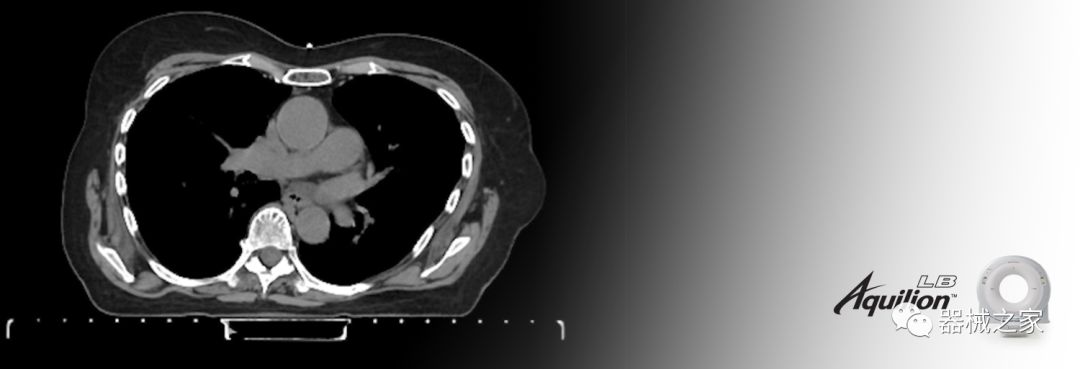

在以患者為中心的放射腫瘤學(xué)領(lǐng)域,計算機(jī)斷層掃描(CT)的可訪問性,可重復(fù)性和靈活性至關(guān)重要。為了建立這些價值,佳能醫(yī)療系統(tǒng)美國公司現(xiàn)在正在擴(kuò)大其放射腫瘤學(xué)CT模擬產(chǎn)品,包括Aquilion Prime SP和Aquilion Lightning 80高級CT系統(tǒng)。除了Aquilion LB之外,Aquilion Prime SP和Aquilion Lightning 80現(xiàn)在還包括放射治療(RT)選項,可為腫瘤學(xué)規(guī)劃提供高質(zhì)量的CT成像和精密工具。

Aquilion LB專為滿足腫瘤學(xué)挑戰(zhàn)而設(shè)計,同時優(yōu)先考慮患者護(hù)理。Aquilion LB的內(nèi)徑為90 cm,能夠幫助復(fù)雜的患者設(shè)置并提高患者的舒適度。CT模擬定位可以輕松鏡像放射治療定位,更加自信。該系統(tǒng)采用0.5 mm x 16排(32層)PUREViSION探測器技術(shù),70 cm視野,AIDR 3D和SEMAR技術(shù)。